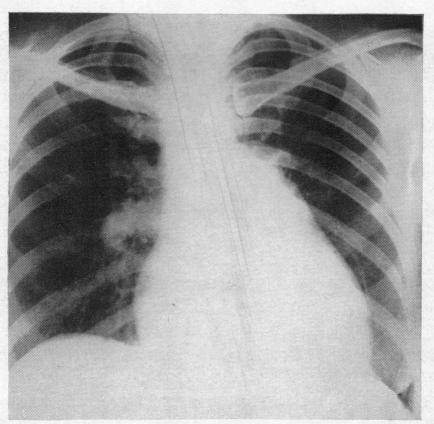

Solitary pulmonary hypertension.

Br Heart J. 1957 Jan;19(1):93-116. doi: 10.1136/hrt.19.1.93.